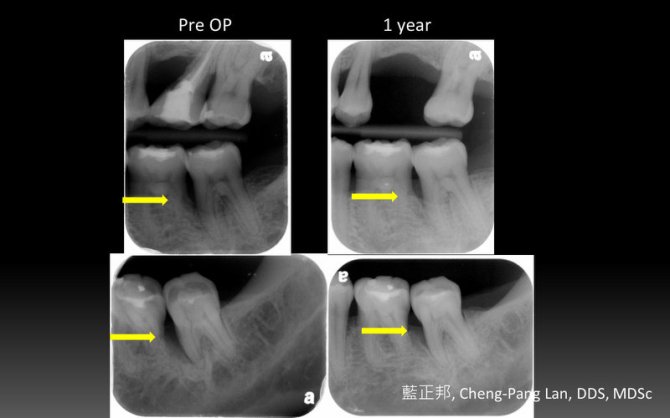

Guided Tissue Regeneration – Case D

This entry was posted in Periodontal Regeneration and tagged Autogenous bone, Collagen membrane, GTR, Intrabony defect, Trap-door. Bookmark the permalink.